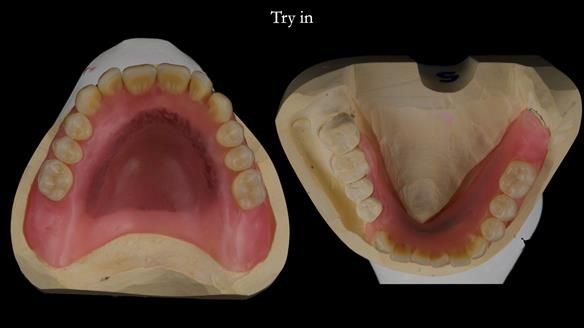

However, once Rowan and I reviewed the remaining metal crown on tooth 46, we realised it would make an ideal abutment for a gasket denture. By reshaping the lingual surface of the crown, we created an excellent gasket seal.

This approach worked far better than the proposed ring-clasp design - improving retention, comfort, and aesthetics while keeping the design clean and simple.

Mary’s upper occlusal plane wasn’t parallel to her interpupillary line, and she specifically wanted that natural asymmetry preserved. Rowan arranged the teeth beautifully, following the exact contour and character of her original smile.

For both the upper and lower dentures, we used Schottlander Enigma Life teeth. I’ve been using these since 2014 and they’ve been outstanding - the surface texture, colour depth, and light reflection are superb. When arranged to mirror the patient’s natural tooth positions, they look completely lifelike.

- The gasket seal around 46 was made using retention.sil 200, producing a precise, cushioned fit.

- Enigma Life teeth provided a natural, individualised appearance perfectly matching Mary’s desired smile.